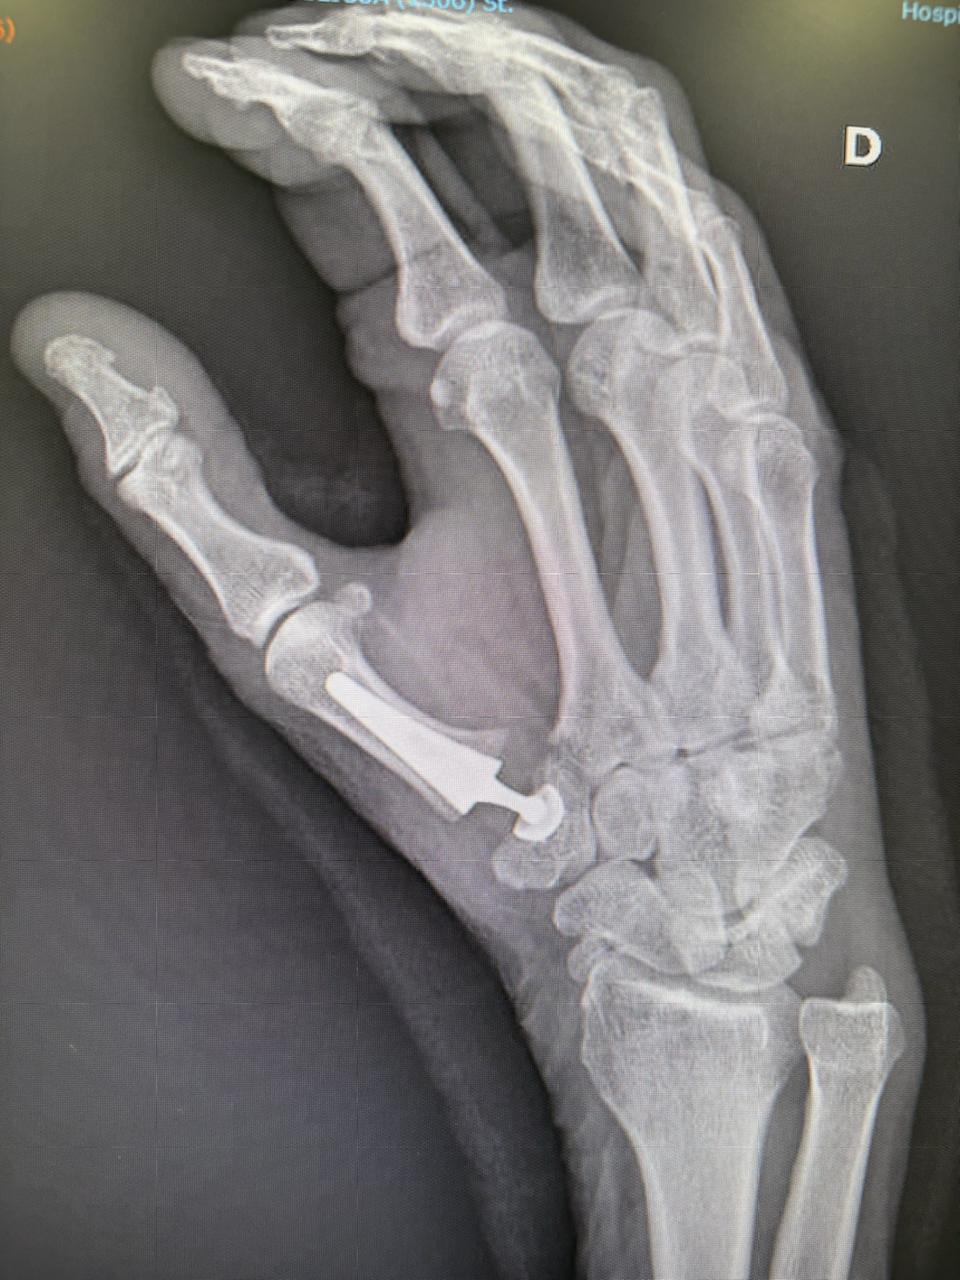

Sustitución/Reemplazo de base del pulgar. Abordaje quirúrgico empleado para la sustitución de la base del pulgar con prótesis modular, esta técnica permite eliminar el dolor por desgaste de tus articulaciones y recuperar la calida de vida que mereces disfrutar.

Reemplazo articular de base de pulgar. Una muestra de como luce la protesis de sustitución de base del pulgar en rayos x, provee una gran estabilidad aun siendo tan pequeña.